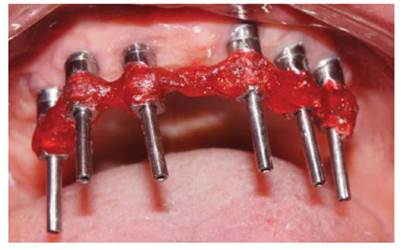

Se procedió a la transferencia de los pilares en el maxilar superior con cubeta abierta y ferulización de transfer (Figura 4), y a la transferencia de la plataforma de los implantes en el maxilar inferior.

Figura 4 Ferulización de transfers

Luego se procedió a la fabricación de la estructura metálica del maxilar superior con la ayuda de una pantalla de silicona obtenida del protocolo reverso, esta estructura presentó un asentamiento pasivo comprobado clínica y radiográficamente luego de realizar los cortes y soldajes necesarios (Figura 5). Se realizó el enfilado para la prótesis híbrida con dientes Ivostar/Gnathostar donde se evaluó estética y fonación. En el maxilar inferior se torquearon los pilares CM recto para la pieza 35 y Pilares angulados (17°) a nivel de piezas 36 y 46 fresados con la ayuda de una guía de colocación de pilares (Figura 6) y se fabricaron coronas de metal cerámica. Para finalizar se procede a la instalación de la prótesis híbrida superior, la cementación de las coronas con cemento temporal y la instalación de una férula de DCM (figura a y b). Finalizado el tratamiento se realizaron controles periodontales y protésicos periódicos donde se comprobó la correcta concientización del paciente en cuanto a su mantenimiento. (Figura 8)

Figura 7 a Instalación de la prótesis híbrida superior